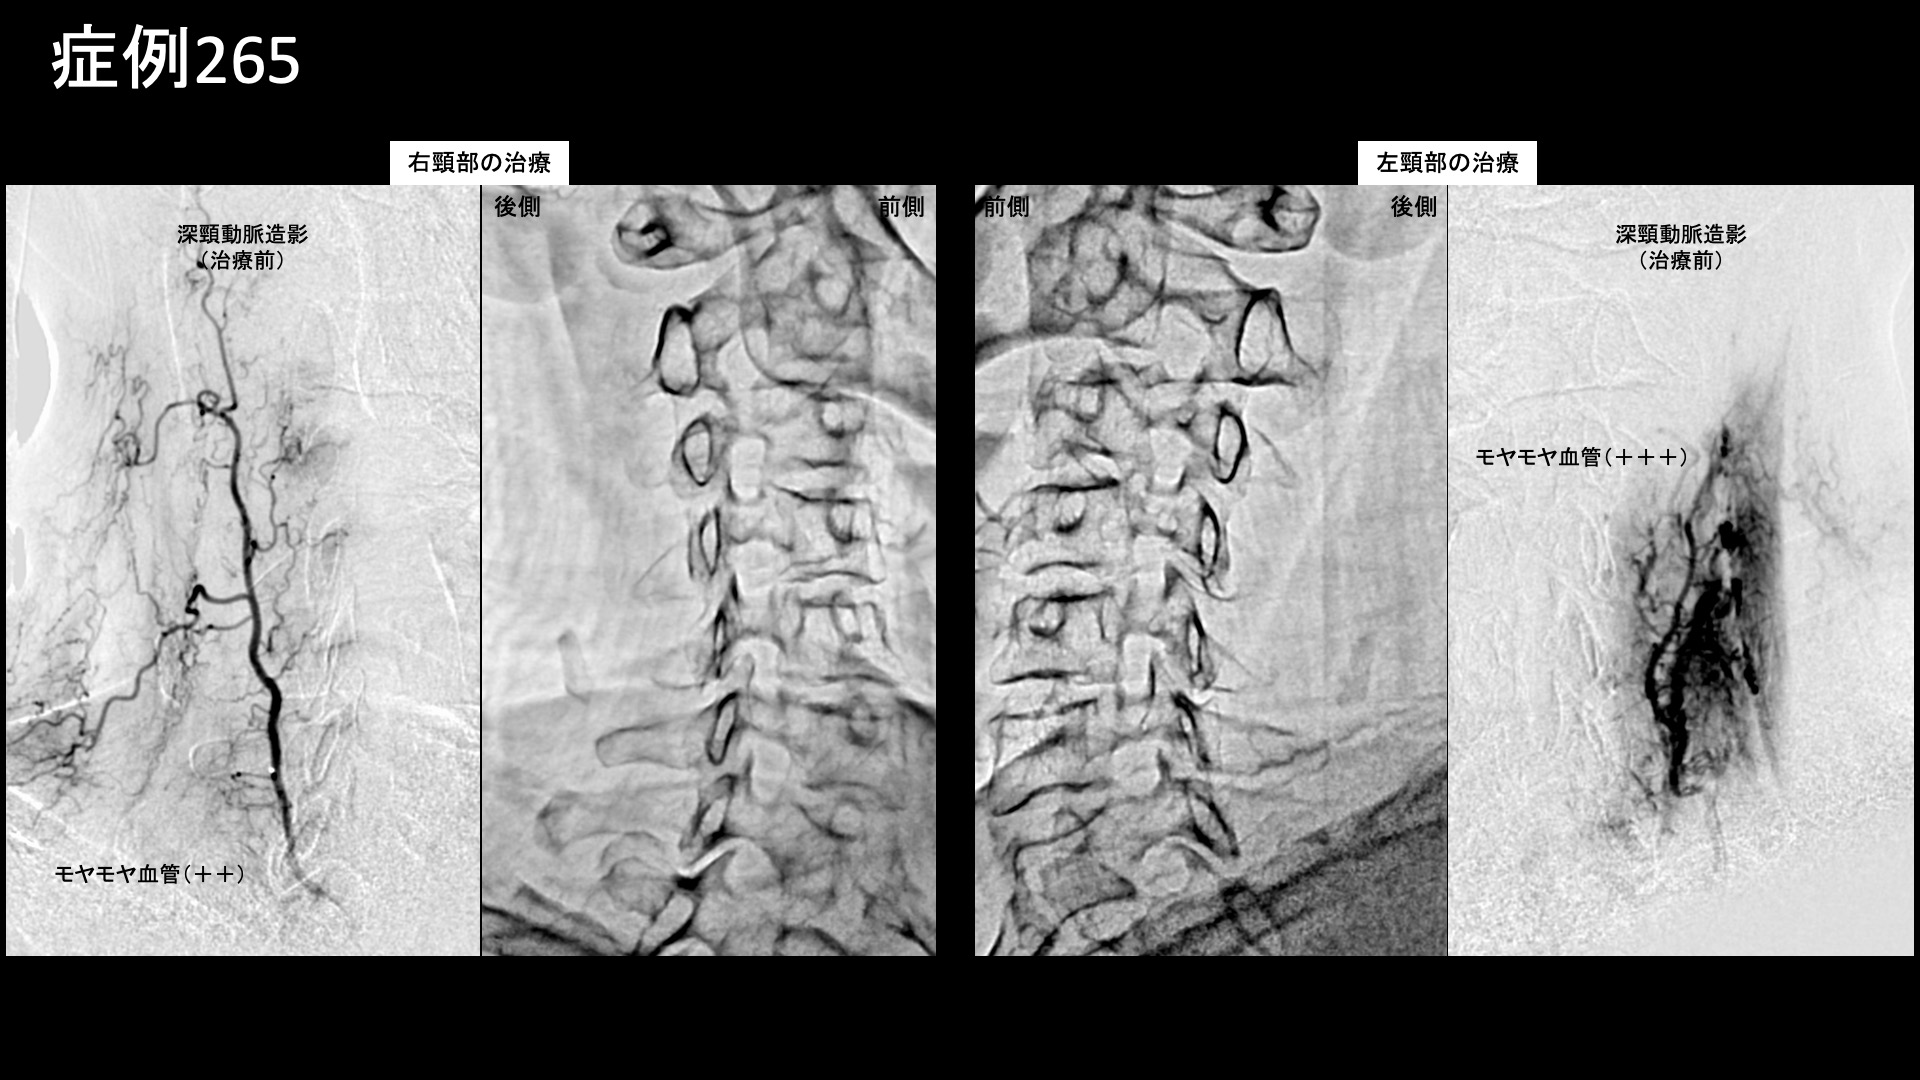

血管造影を行うと、首こりの主要責任血管である深頸動脈で、左側優位にモヤモヤ血管が濃染像として描出されました。治療後は画像上速やかに消失しました。その他肩こりの血管など複数箇所の治療を行い終了しました。

治療前画像:損傷を受ける、あるいは繰り返しのストレスにより発生した異常な新生血管

治療後画像:カテーテルを用いて塞栓物質を血管内に投与し新生血管を塞いだ状態